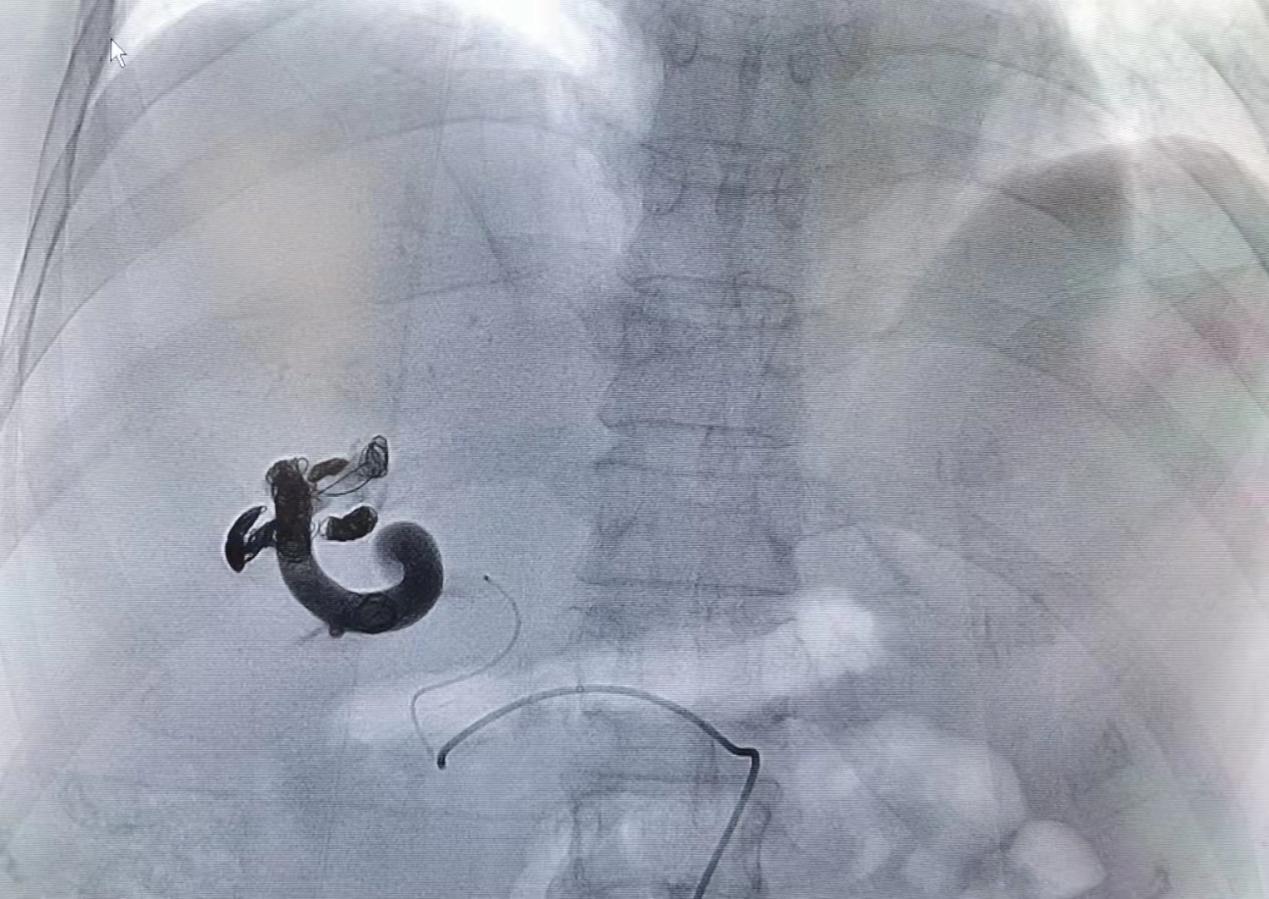

图三、四:弹簧圈联合组织胶栓塞靶血管